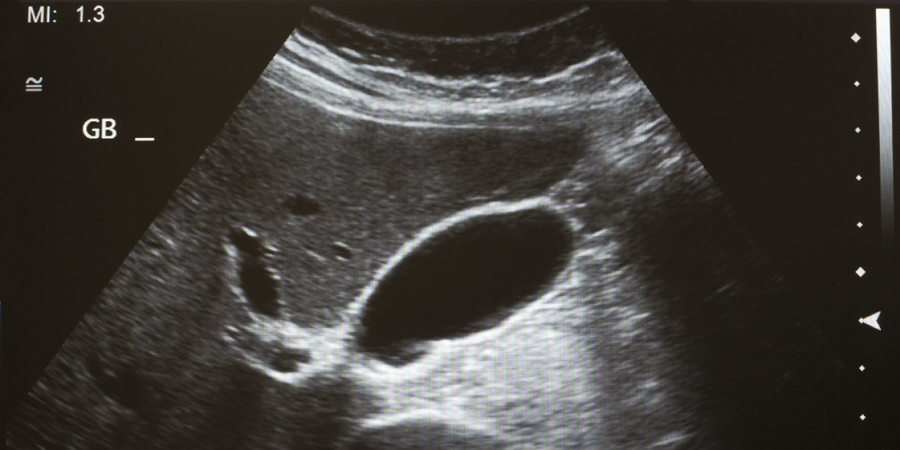

Echo’s door de huisarts lijken betrouwbaar

Weinig huisartsen maken zelf echo’s, maar na een cursus echoscopie blijken ze eenvoudige diagnoses zelf te kunnen stellen. De beoordeling van getrainde huisartsen komt overeen met die van een specialist. Dat blijkt uit Scandinavisch onderzoek.